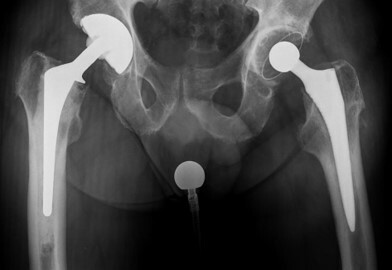

Η θεραπεία για τη περιπροθετική λοίμωξη εξαρτάται από τη σοβαρότητα της κατάστασης και την υποκείμενη αιτία. Οι επιλογές περιλαμβάνουν: